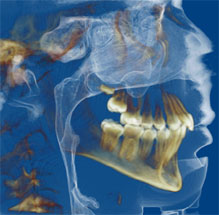

The most recent radiographic innovation available is 3-D Cone Beam Technology, which are full head scans taking only 8.5 seconds. We can limit your radiographic exposure while providing all the images required in orthodontics plus a greater ability to pinpoint impacted teethevaluate airwayand aid in placement of implants. Cone Beam CT will likely be the standard of care in orthodontics in the near future. We are working with other offices when we need these special scans and we look forward to having this new technology in our office.

3D Cone Beam images allow us to obtain a more "user-friendly" picture to pinpoint exactly where teeth are or show the airway in a way we haven't been able to visualize in the past.